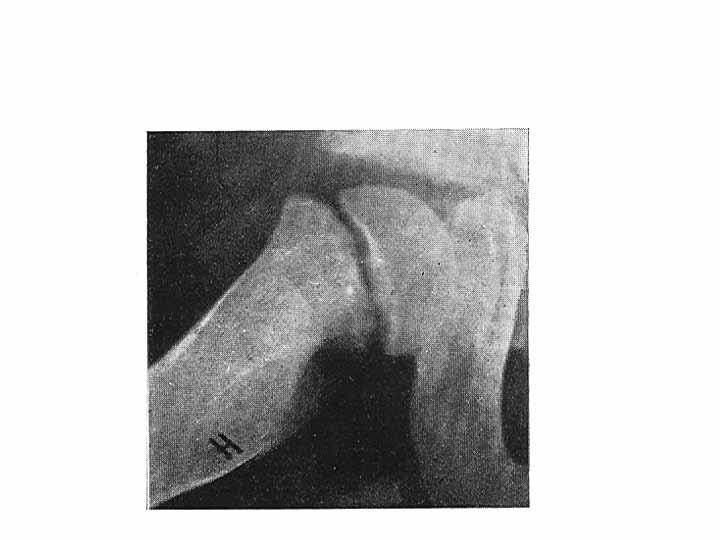

5-årig pojke som sedan en månad haltat och verkat ha ont i höger fot. Inget trauma, ingen feber eller infektion. CRP u.a.

Pojken verkar frisk men går med hälta och vill inte avveckla steget riktig med höger fot. Vid klinisk undersökning finner man måttlig ömhet över mellanfoten. Rörelseomfånget i fotleden och subtalärt är normalt.

Rtg , v.g. se bild.

a. Diagnos? ( 1p)

b. Behandling ? (1p)

c. Naturalförlopp ?(1p)

Fråga 9.

a. Mb. Köhler 1 ( avaskulär nekros av os naviculare)

b. Hålfotsinlägg eller en tids behandling med gånggips brukar lindra besvären, som försvinner inom några månader.

c. Till skillnad från avaskulära nekroser på andra lokalisationer restitueras konfigurationen av os naviculare spontant. Röntgenbilden normaliseras inom loppet av några år och sjukdomen ger inga sena komplikationer.